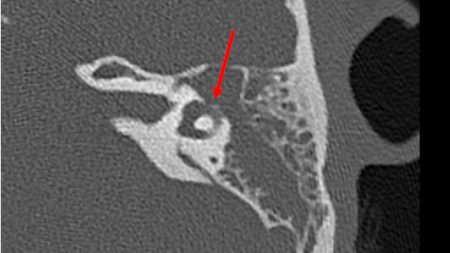

- tomografia computadorizada (TC) ou ressonância nuclear magnética (RNM) cranioencefálica